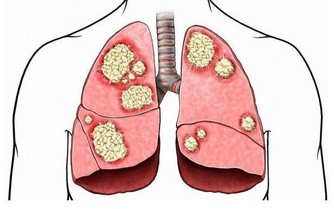

三叉神經痛的誘發因素有很多,可能與飲酒、頭部長期受寒、飲食過於粗糙有關,還可能與一些疾病相關,比如說癌症、顱內性疾病,這些原因都有可能會引起三叉神經痛。